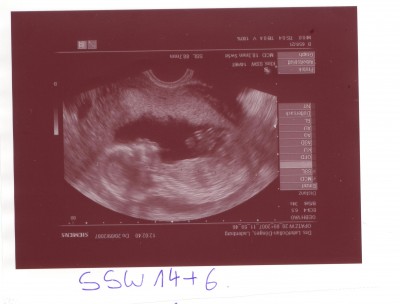

Ach so unser Knödel wollte euch auch mal winken

Knödelhand  SSW 14+6.JPG